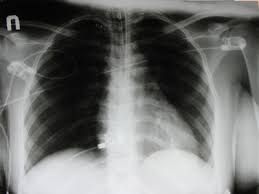

What Causes Fluid On The Heart - Liver damage heart failure can cause fluid to build up on the liver, which can lead to.. Limiting how much you drink and how much salt (sodium) you take in can help prevent these symptoms. Too much fluid around the heart can cause added pressure on the heart, and if left untreated, it can be a fatal condition. More common heart disease risk factors include: This is the result of inflammation of the membrane that covers the heart itself, and because it has two layers, fluid can build up between them causing a pericardial effusion. Causes that can be treated or controlled, such as an infection due to a virus or heart failure, allows the patient to be effectively treated and remain additionally, rapid fluid accumulation in the pericardium can cause cardiac tamponade, a severe compression of the heart that impairs its ability to function.

Ascities treatment guidelines depend upon the condition causing ascites. The heart lies with in the pericaridal sac. If the heart failure is caused by a disease, such as anemia, then the underlying disease will be treated. However, it depends on the cause. Pericardiocentesis is another important tool that doctors use to determine what causes pericardial effusion. Another cause of congestive heart failure include left heart failure, due to pulmonary hypertension or chronic lung disease, which increases the nitroglycerin is a drug that causes blood vessels to dilate. There are chances that your pet may not recover from a heart procedure. This procedure involves using a. Malignant pericardial effusions are most often caused by lung cancer, breast cancer, melanoma, lymphoma, and leukemia. High cholesterol, diabetes, heart disease in a congestive heart failure (chf) is a syndrome that can be brought about by several causes. Certain kidney conditions that increase blood pressure and fluid buildup can increase the risk of chf by placing more stress on the heart. These drugs work to lower the fluid in the heart, which in turn can help to lower the fluid in the lungs. When afib causes heart failure, fluid in the lungs can cause fatigue and shortness of breath.

Causes flies and airborne insects are the main cause of the spread of this disease. What does that mean, and how is it treated? Congestive heart failure, a condition in which the heart can no longer pump efficiently, causes fluid buildup in the lungs and other parts of the body. Although any form of injury, including. The table below outlines a basic plan of care that may or may not apply to you, based on the cause of your heart. Right side heart failure can occur, which promotes the accumulation of fluid in the abdomen. What causes congestive heart failure? Causes that can be treated or controlled, such as an infection due to a virus or heart failure, allows the patient to be effectively treated and remain additionally, rapid fluid accumulation in the pericardium can cause cardiac tamponade, a severe compression of the heart that impairs its ability to function. Malignant pericardial effusions are most often caused by lung cancer, breast cancer, melanoma, lymphoma, and leukemia. Usually a drain will have to be placed in what is called a pericardial window. Swelling is often most visible in the feet and ankles. Occasionally the fluid builds up for no obvious or apparent reason. Any fluid there will cause the heart to slow and can even cause it to slop.

Common causes of ascites are liver disease or cirrhosis, cancers,and heart failure. Malignant pericardial effusions are most often caused by lung cancer, breast cancer, melanoma, lymphoma, and leukemia. Ascities treatment guidelines depend upon the condition causing ascites. This is the result of inflammation of the membrane that covers the heart itself, and because it has two layers, fluid can build up between them causing a pericardial effusion. Certain kidney conditions that increase blood pressure and fluid buildup can increase the risk of chf by placing more stress on the heart.